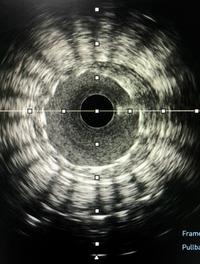

Alors que l’intervention coronaire percutanée (PCI) guidée par imagerie endo-coronaire (échographie ou tomographie par cohérence optique) [...]